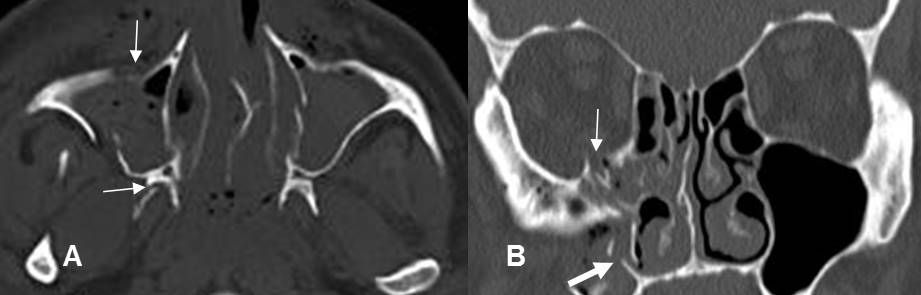

Fig 190. Fractura de Jefferson.

A y B: TAC axial. Fractura conminuta del arco anterior y de la parte derecha del arco posterior de C1. Existen fragmentos libres dentro del canal y compromiso del agujero vertebral en el lado izquierdo. (Flecha gruesa).

C: TAC reconstrucción coronal. Desalineación entre las masas laterales de C1 y C2.